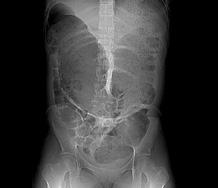

Niedrożność mechaniczna jelita grubego w przebiegu endometriozy - opis przypadku

Mechanical ileus of large bowel in course of endometriosis - a case report

Surgery

Radoch M., Pawłowski W., Guzel T.

Endometriosis is a disease in which endometrial cells are located outside the uterine cavity. It affects women of reproductive age reproductive age. Rarely, endometriosis foci localize in the gastrointestinal tract. Intestinal endometriosis most often occurs in the large intestine, sometimes causing mechanical obstruction.